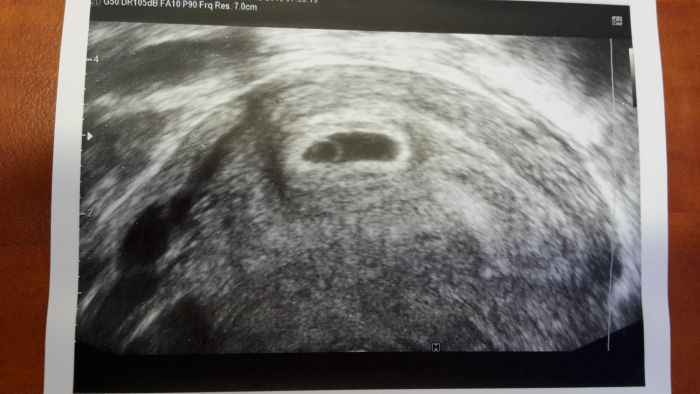

Ahoj, tak muj utz v 5+0, jen pekne spatna fotka, blbla jim tiskarna :-( ale pry to taky odpovida :-)